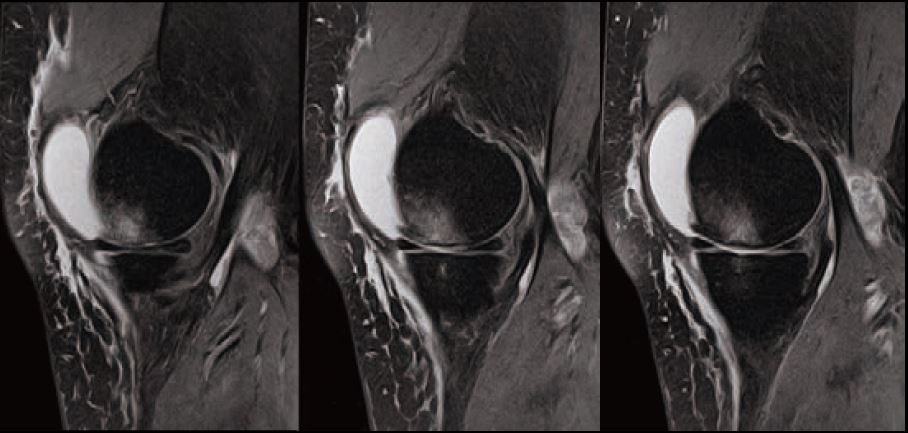

Випадок 2. Коліно високої роздільної здатності

Чоловік 26 років проходить посттравматичну діагностику, є скарга на біль.

• Відсутність травматичного пошкодження.

Рис. 5 Sg FSE T2 FS і Sg FSE T1, товщина зрізу 3 мм, роздільна здатність 0,2 мм.

Рис. 6 Sg косий FSE T2, товщина зрізу 2 мм, роздільна здатність 0,2 мм.